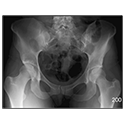

NEUROANATOMY